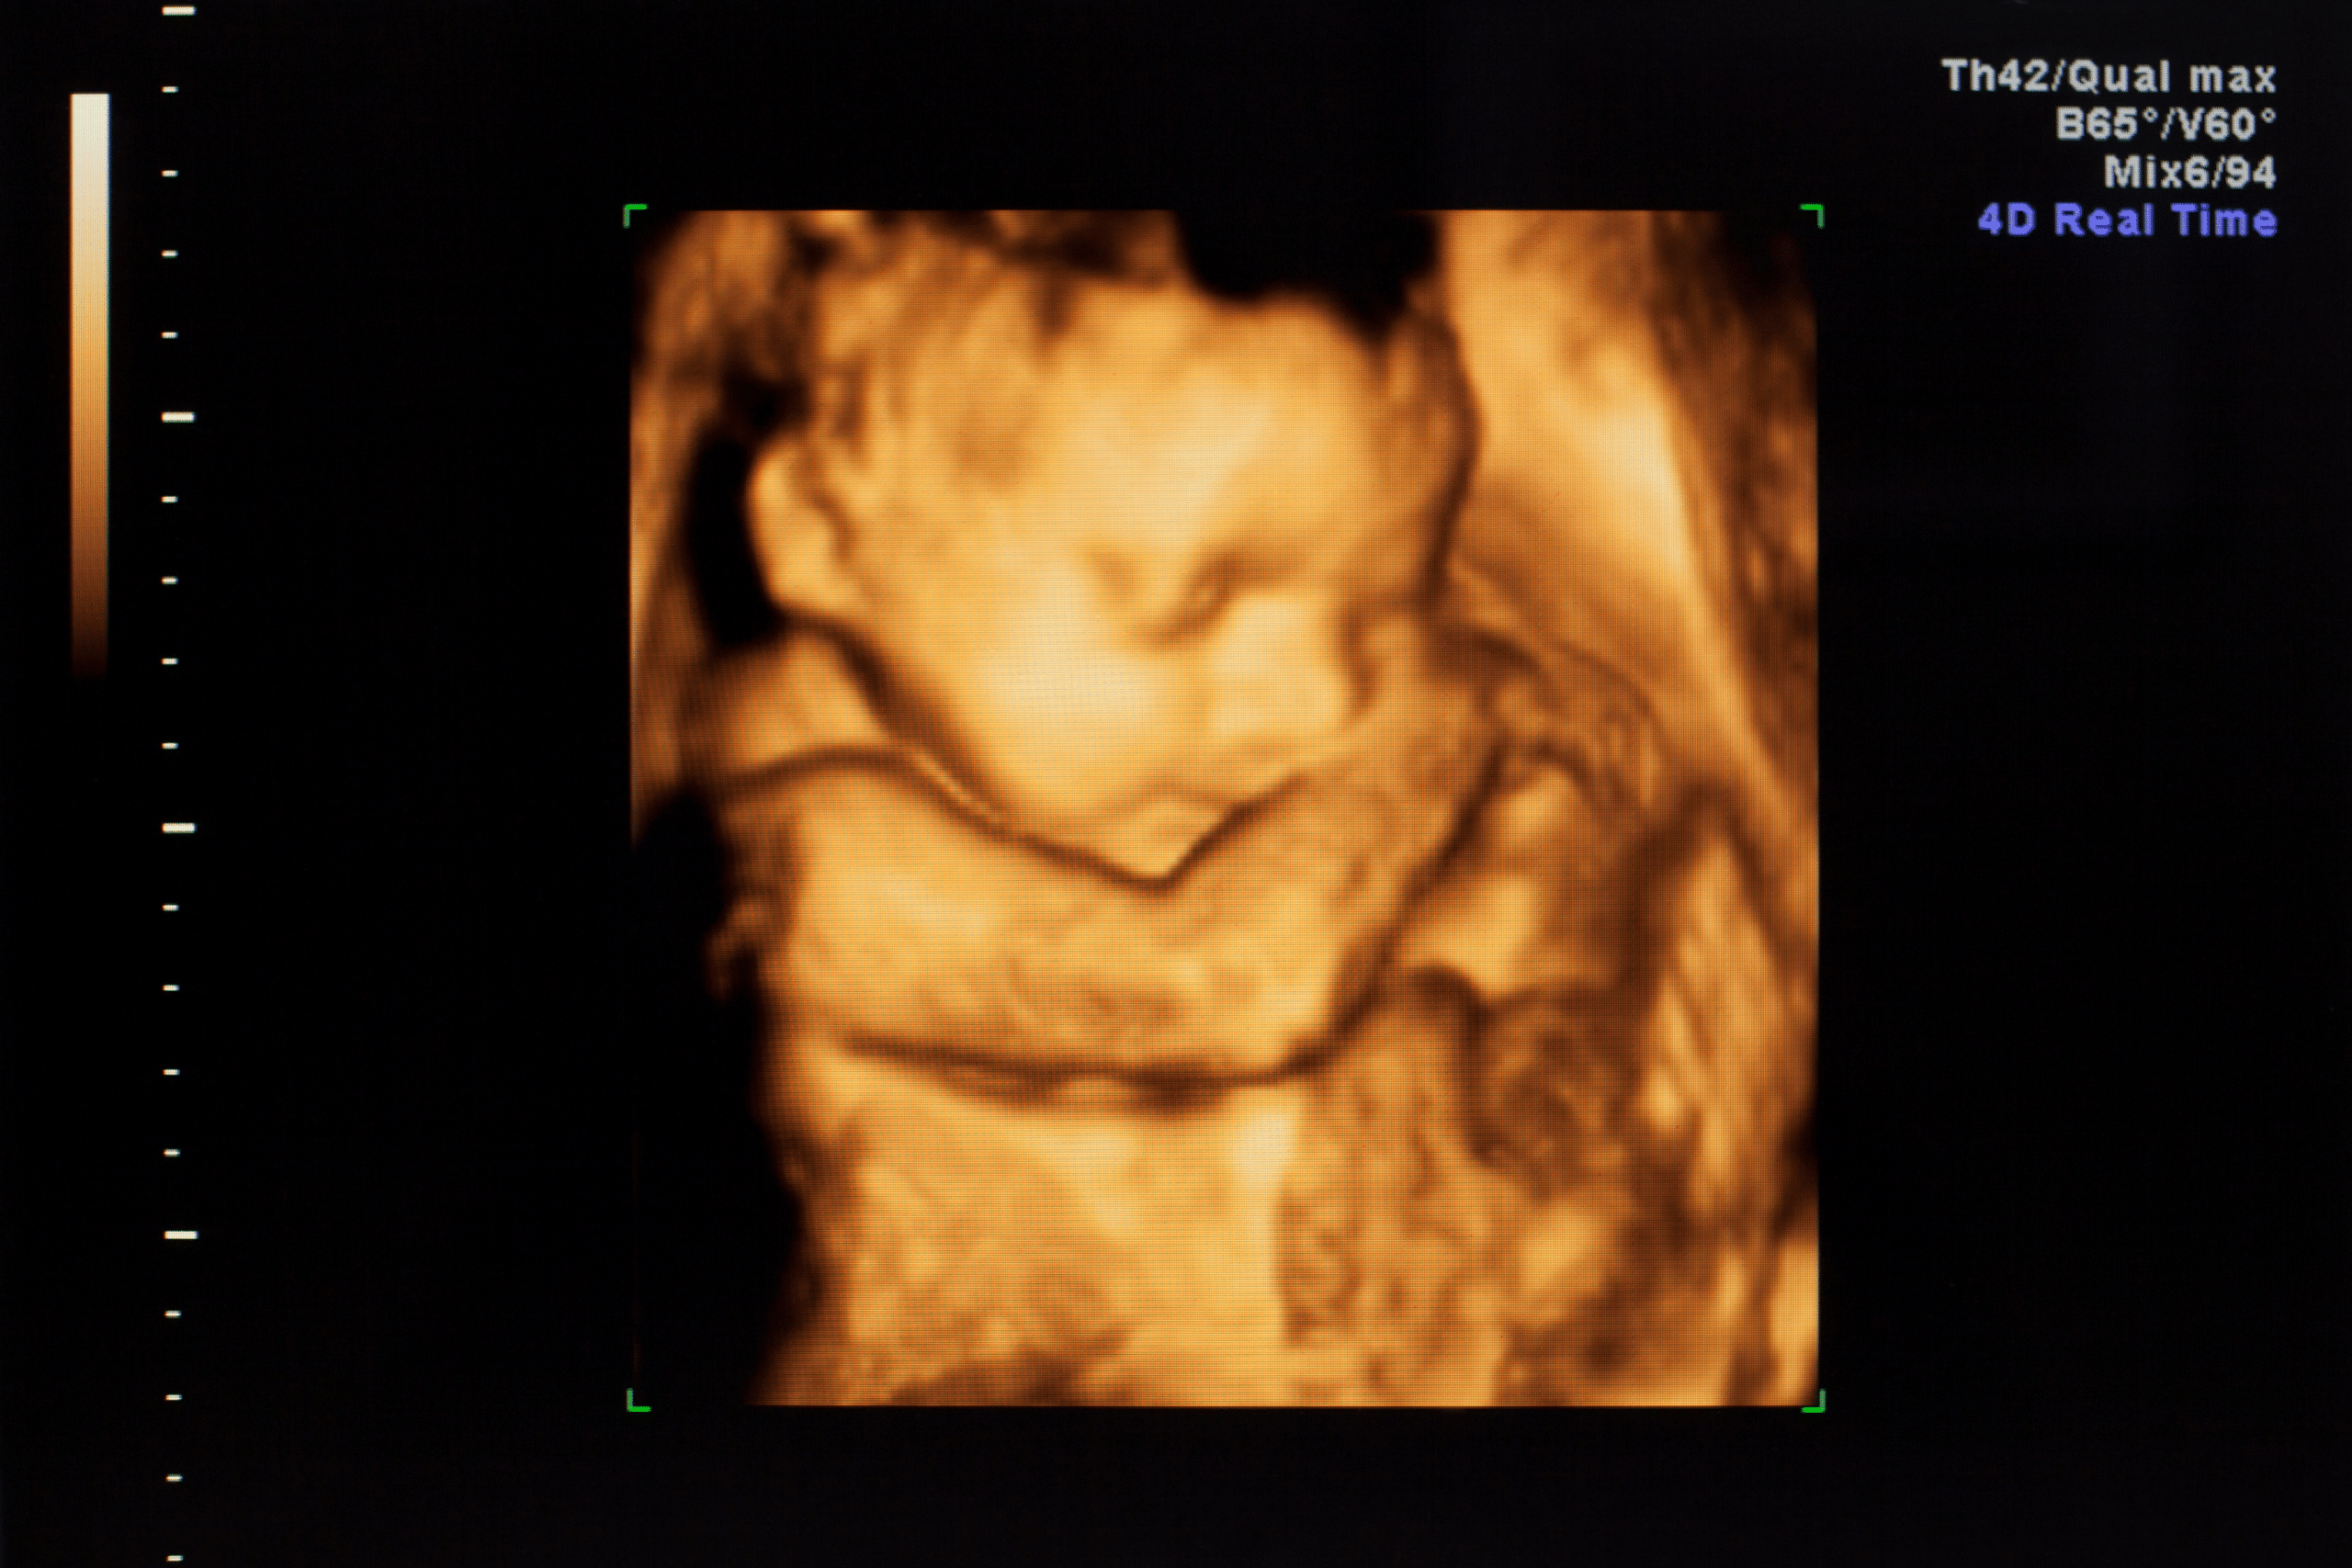

Sérvműtét a Platán Magánklinikán

A sérvek döntő hányada a hasfalat érinti, felnőtteknél a leggyakoribb típusú sérv a lágyéksérv. A sérvek égő, szúró, éles fájdalmat okozhatnak, melyet elsősorban a hashártyára és a bélfodorra gyakorolt húzó erő okoz, ezek az idő előre haladtával növekszenek, esztétikai panaszokat is okozva. A sérvek – hasi, köldök vagy lágyék- sebészi betegségek, melyekre a megoldásokat egyénre … Olvass tovább